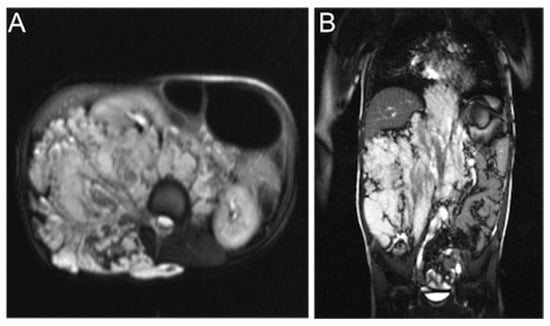

We determined the size, location, affected tissue planes, morphological appearance, and presence of phleboliths of each VM based on the MRI studies. Because VMs are irregularly shaped and often diffusely infiltrate normal tissues, exact dimensions could not be obtained. We measured the greatest diameter in any of the three planes and graded it as small (<5 cm), medium (5–10 cm), wide (10–25 cm), or extensive (>25 cm). Lesion location was defined as head/neck, trunk, or extremities. According to the affected tissue planes, the depth of the lesion was categorized into three groups: (1) superficial lesions confined to subcutaneous fat, (2) lesions with an intramuscular, -osseal, or -articular component, and (3) deep lesions with an intra-abdominal, retroperitoneal, or intra-thoracic component. We divided the malformations into two categories by morphology: (A) discrete, relatively well-demarcated malformations and (B) diffuse, phlebectatic malformations (Figure 1). Phleboliths were defined as small intraluminal foci of signal-voids, visible both in T1- and T2-weighted sequences, consistent with calcifications.

Figure 1. An example of the two different morphological appearances of VMs in MRI. (A) A discrete and well-demarcated VM in the thigh muscles. (B) A diffuse VM of the right forearm.

Figure 2. Axial (A) and coronal (B) T2-weighted MR images of an extensive VM affecting the retroperitoneum and spinal muscles and dislocating the bowel and the right kidney to the left.